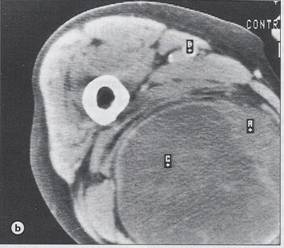

Chondrosarcom

b)humerus dr

proximal, distructie corticala, extensie in parti moi